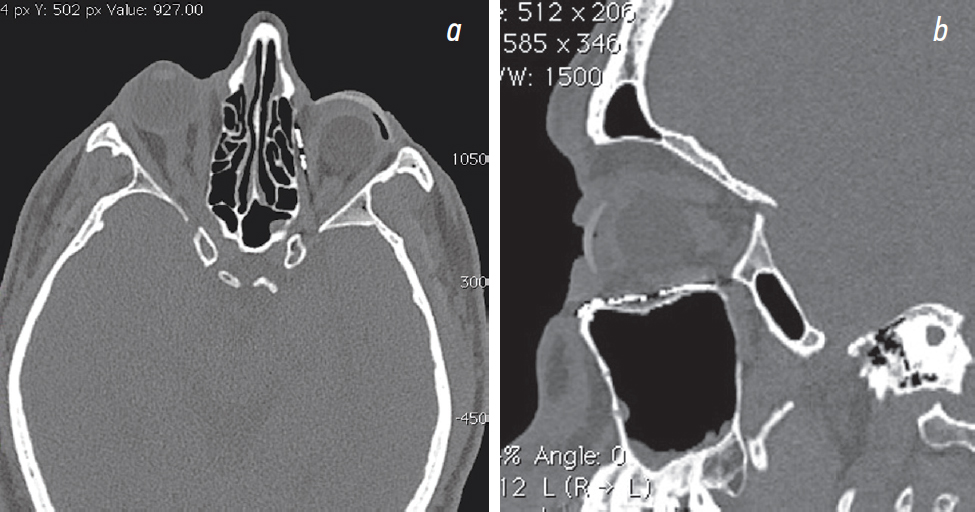

Fig. 7. Multispiral computed tomography: а — axial view; b — sagittal view. Titanium mesh over the defect zones. Prosthesis is congruent to the stump shape / Рис. 7. Мультиспиральная компьютерная томография: а — аксиальный вид; b — сагиттальный вид. Сетка над зонами дефектов. Косметический протез конгруэнтен передней поверхности опорной культи